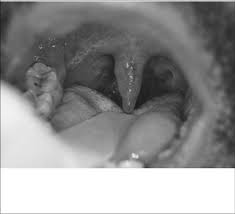

About 2 hours later uvular oedema completely disappeared along with resolution of symptoms figure 2. Five years after surgery Cheifetz says about 50 percent of patients already have clinical recurrence of Crohns. This usually happens in adult women with no other health problems and are called an uncomplicated UTI.

We report two cases of Quinckes disease an isolated form of angioneurotic edema involving the uvula that is induced by several factors including foods drugs and inhalants. Eventually these diabetes complications may become debilitating or perhaps life-threatening. People with Crohns disease can have the same life expectancy as those without the condition.

At 6 months follow-up the patient remained symptom free. According to the Crohns and Colitis Foundation around 58 percent of people develop colorectal cancer within 20 years of a diagnosis of ulcerative colitis. Although Quinckes disease has prominent oral manifestations it has only rarely been described in the dental literature.